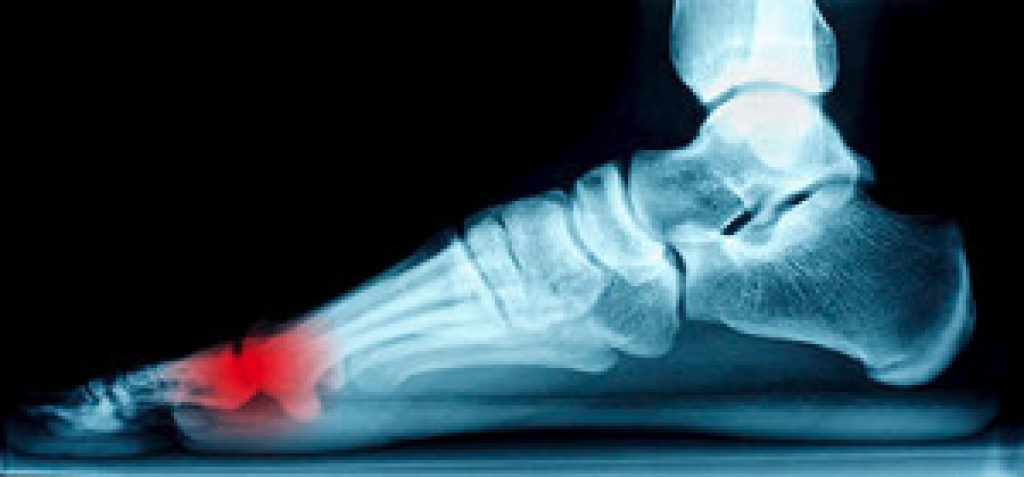

The Achilles tendon is a tendon that connects the lower leg muscles and calf to the heel of the foot. It is the strongest tendon in the human body and is essential for making movement possible. Because this tendon is such an integral part of the body, any injuries to it can create immense difficulties and should immediately be presented to a doctor.

There are various types of injuries that can affect the Achilles tendon. The two most common injuries are Achilles tendinitis and ruptures of the tendon.

Achilles tendon injuries are diagnosed by a thorough physical evaluation, which can include an MRI. Treatment involves rest, physical therapy, and in some cases, surgery. However, various preventative measures can be taken to avoid these injuries, such as: